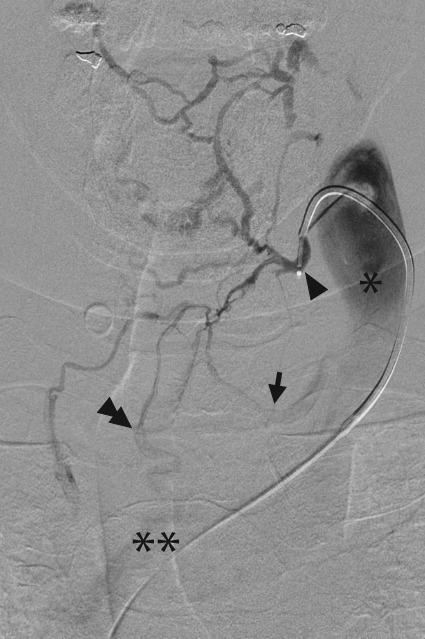

Venous sampling is the gold standard for localizing abnormal hormone secretion in several endocrine disorders. The most common indication for venous sampling is in the workup of primary aldosteronism, adrenocorticotropic hormone-dependent Cushing's syndrome, and hyperparathyroidism. In experienced hands, venous sampling is safe and accurate. This review discusses the role of venous sampling in the workup of endocrine disease, describing the underlying anatomy and pathophysiology, as an understanding of these concepts is essential for technical and clinical success.